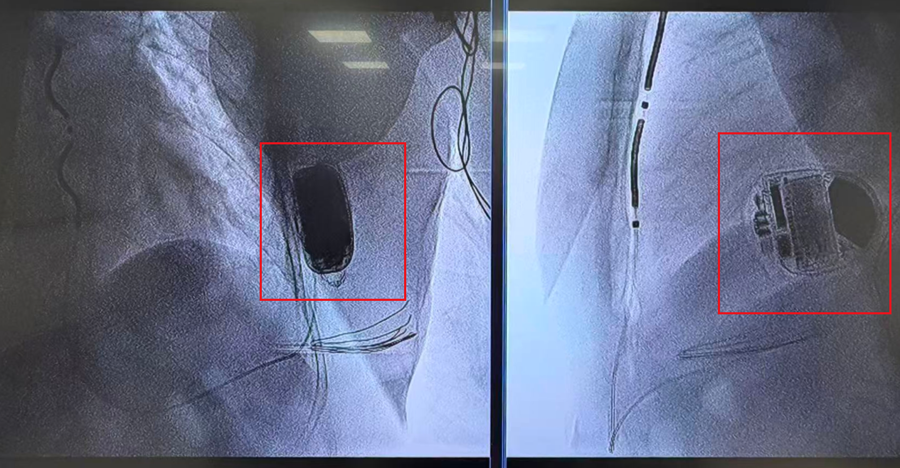

红框处为胡阿姨植入的最新型2.0版的血管外植入式心律转复除颤器

这个最新型除颤器,从逻辑上属于“血管外除颤器”,但和传统相比,新型技术发生了升级,医生们会将除颤器的电极隐藏在胸骨和心脏中间,像“创可贴”一样覆盖在心脏表面,这样,既解决了血管受损问题,也因缩短距离,大大提升了除颤器的能量作用。2.0版的除颤做到了一举两得!它已在2025年6月经国家药品监督管理局获批上市,是目前全球最新的植入式除颤系统。